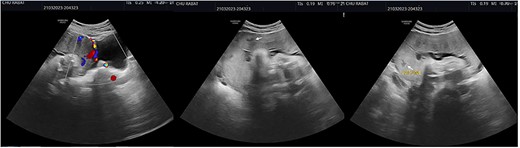

We report the case of a 30-year-old woman who had a C-Section 2 years earlier for fetal macrosomia. She presented in our department for a normal routine fetal ultrasound that identified some intra-placental lacunae as well as the protrusion of placental tissue beyond the uterine myometrium, with a discontinuity in the urinary bladder wall and the extension of Doppler vascularity between serosa and the bladder (Fig. 1). Abnormal placental insertion was thus suspected and a placental MRI was realized to confirm the diagnosis.

Ultrasound showing intra-placental lacunae (white arrows) as well as placental tissue protrusion beyond the uterine myometrium, as well as urinary bladder wall discontinuity and the extension of Doppler vascularity between serosa and the bladder (Fig. 1).